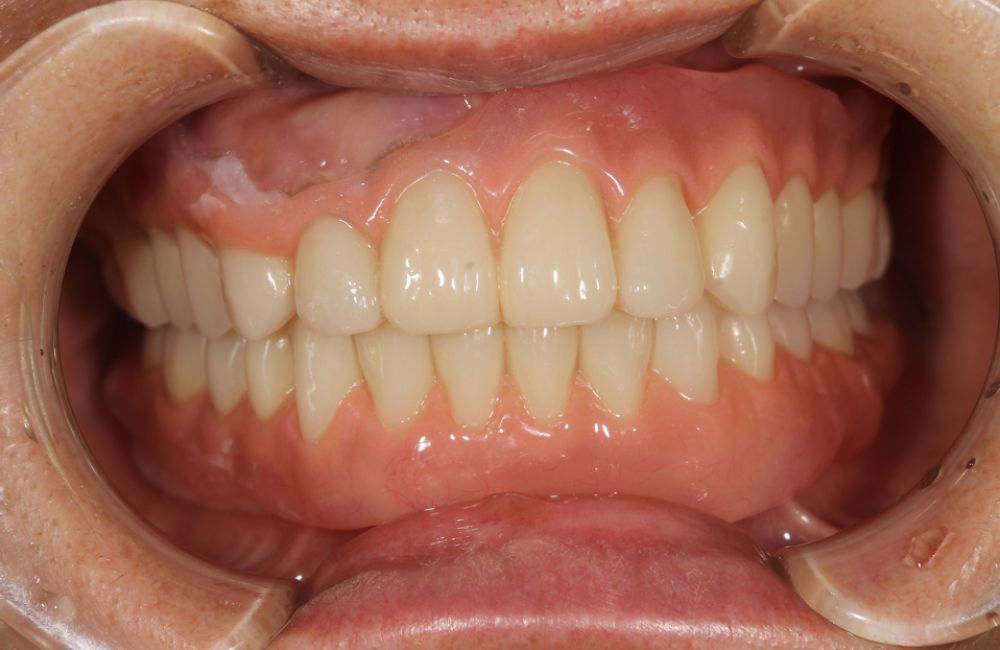

インプラントオーバーデンチャーの装着前と装着後

このように、インプラントオーバーデンチャーの治療によって、噛む力や見た目を大きく改善することができました。

インプラントオーバーデンチャー装着